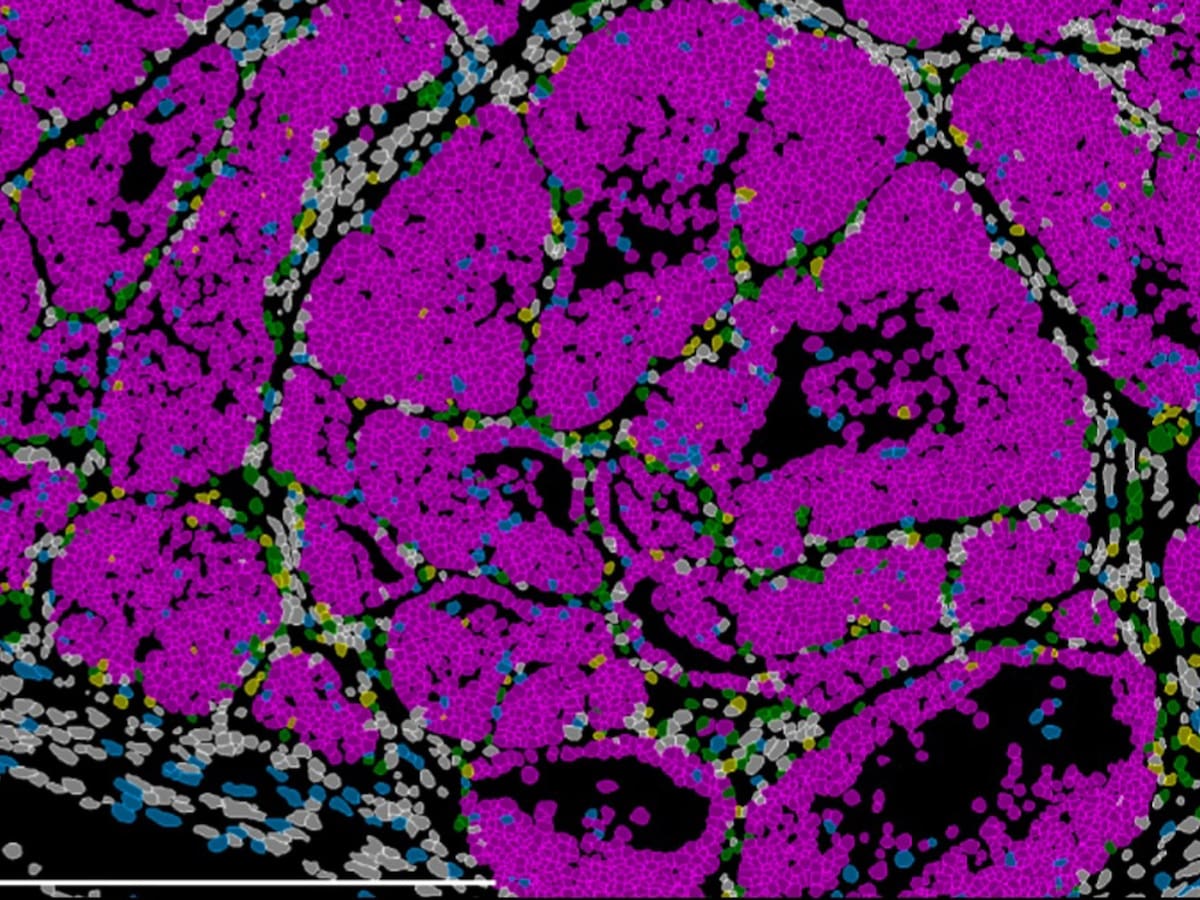

La profesora de Investigación CSIC en el Instituto de Neurociencias CSIC-UMH ha dirigido un estudio cuyos resultados abren la puerta a impedir que las células tumorales alcancen un estado peligroso